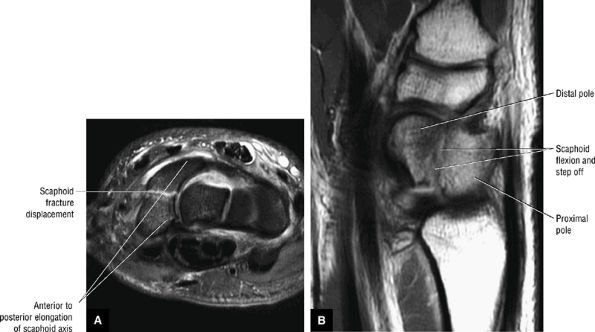

Perilunar instabilities include lesser arc injuries (primarily ligamentous [e.g., scapholunate or lunotriquetral injuries]) and greater arc injuries (primary osseous [e.g., scaphoid fracture]).

Acute injuries (less than 6 weeks) may be classified as either stable injuries (partial ligament disruption) (Fig. 10.93) or dynamic or static unstable injuries (complete ligament disruption) (Fig. 10.94).